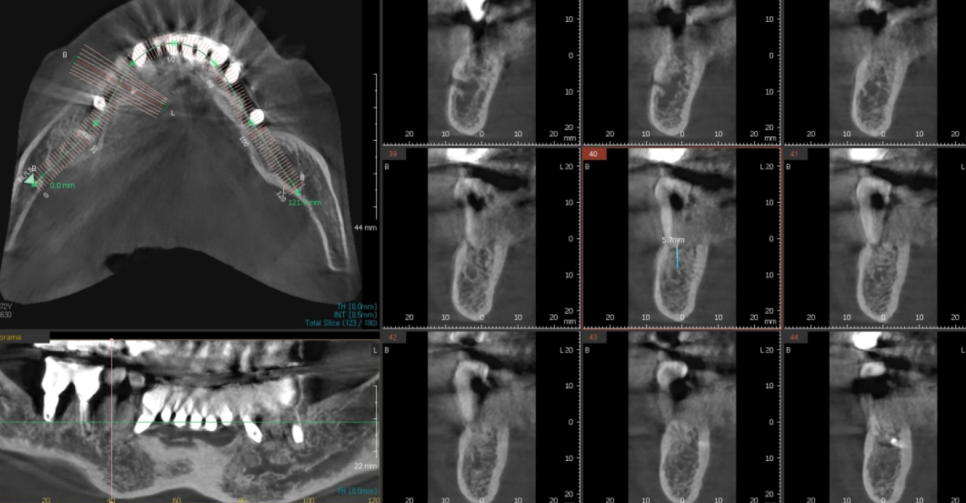

전신질환을 가진 환자분의 경우

덕소 치과에서 특히 신경쓰는데요.

해당 환자분도 내과 협진, CT 분석

철저하게 진행하였습니다.

그리고 발치 후 당일 뼈이식을 진행 후

뼈가 1차적으로 차면

그때 임플란트 수술을 진행하기로 하였습니다.